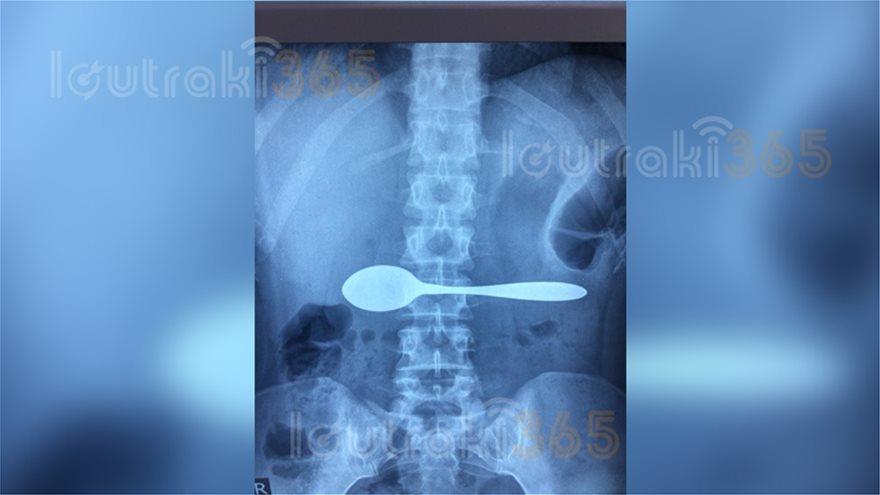

Η 35χρονη, τους εξήγησε ότι καταλάθος, κατάπιε ένα κουτάλι. Οι γιατροί του Νοσοκομείου, της είπαν να βγάλει αμέσως ακτινογραφία για να διαπιστώσουν αν όσα έλεγε η Κορίνθια ασθενής, ανταποκρίνονταν στην πραγματικότητα.

Και όμως. Μόλις η ακτινογραφία επιβεβαίωσε τα όσα έλεγε η 35άχρονη, οι γιατροί του Νοσοκομείου Κορίνθου την έστειλαν αμέσως σε εφημερεύον Νοσοκομείο της Αθήνας, καθώς έπρεπε να εξετασθεί από γαστρεντερολόγο που δεν υπήρχε στο Νοσοκομείο Κορίνθου.

Η ακτινογραφία της 35χρονης από το Ξυλόκαστρο:

Η ακτινογραφία 35χρονης στην Κόρινθο άφησε... άφωνους τους γιατρούς